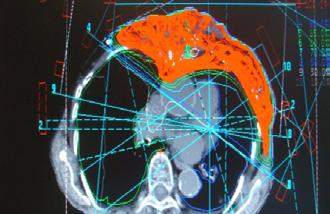

Abstract. Progresele realizate în aplicarea radiațiilor au făcut posibile noi abordări pentru cancerul local avansat. Procesul de „remodelare” este acum o realitate, iar vindecarea locală a tumorii local avansate doar prin radioterapie cu doze mari este acum posibilă. Pe baza tehnicilor moderne de iradiere, cum ar fi IMRT de tip VMAT, Rapid Arc sau Tomoterapie, distribuția dozei conform cu forma volumului tumoral și aplicarea de doze totale mari a făcut posibil procesul de „remodelare” la nivelul țesuturilor moi. Vă prezentăm din propria noastră experiență rezultatul radioterapiei a două tumori mamare local avansate pentru care a fost obținut clinic un control tumoral. Acest lucru a fost posibil datorită aplicării de doze curative de 70 – 72 Gy. În aceste cazuri a fost obținut un control tumoral cu refacerea structurilor invadate. Acest proces de refacere este definit ca „REMODELING“. Etapele vindecării și efectele radioterapiei la nivelul țesutului tumoral și peritumoral (tumor microenvironment – TME) sunt descrise.

Planul de iradiere a pacientei din cazul nr. 2 a fost efectuat la secția de fizică medicală din Centrul de Radioterapie Amethyst din Otopeni.

Planul de iradiere a fost executat după efectuarea unei examinări CT și delimitarea volumelor țintă și optimizarea planului de iradiere, cu aplicarea dozei dorite la nivelul tumorii mamare local avansate cu implicarea tuturor țesuturilor până la rebordul costal.

Evoluția din timpul radioterapiei externe. Înainte de inițierea radioterapiei externe (stânga), cu planul de iradiere aplicat (în mijloc – cu roșu Volumul Țintă iradiat) și după finalizarea radioterapiei. Aplicați au fost 72 Gy.

Evoluția clinică de la începutul radioterapiei și după terminarea ei este redată în figura de mai sus.

Evoluția din timpul radioterapiei externe. Înainte de inițierea radioterapiei externe (stânga), cu planul de iradiere aplicat (în mijloc) și după finalizarea ra-

În literatura de specialitate sunt indicate în cazul tumorilor mamare local avansate regimuri de iradiere cu doze paliative extrem de diferite (10 x 3 Gy, 20 x 2 Gy, 25 x 2 Gy). Noi am aplicat doze curative de 70 -72 Gy.

În concluzie: Progresul în radioterapie este rezultatul îmbunătățirii metodelor imagistice (CT, RMN, PET / CT) și a metodelor realizate în calculul planului de iradiere și de aplicare a iradierii. Tehnicile moderne de radioterapie sunt toate bazate pe intensitatea modulată a fascicolelor (IMRT), ca de exemplu: VMAT (volume modulated arc therapay), Rapid Arc și Tomoterapie. La AMETHYST RADIOTHERAPY CENTER, standardul nostru este administrarea dozei optime la nivelul bolii microscopice (CTV) și macroscopice (GTV) și administrarea unei doze limitate la nivelul organelor cu risc crescut la iradiere, cum a fost în cazul unui cancer mamar local avansat,. Controlul local al tumorii cu efecte secundare acute și tardive reduse fac acum posibilă îmbunătățirea calității vieții acestor pacienți care sigur în alte clinici nu sunt iradiați cu doze locale curative.